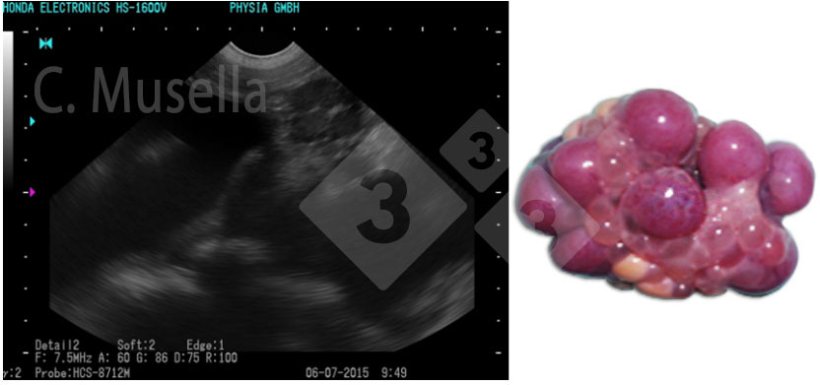

Le diagnostic de kystes ovariens uniques ou multiples est relativement simple, bien que l'identification complète du type de kyste par échographie ne soit pas toujours certaine.

Figure 3. Ovaires polykystiques.